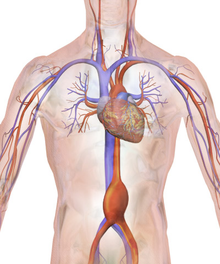

Risk factors include family history, high blood pressure, high cholesterol, smoking, and injury of the blood vessel.[1] While any artery may be affected, they most commonly occur in the aorta (AA).[2] Other types include brain, popliteal artery, mesenteric artery, coronary artery, and splenic artery.[1][2] Diagnosis is based on medical imaging.[1]

Management may include lifestyle changes and surgery.[1] When surgery is recommended depends on the artery in question.[2] Repair of AAAs is generally recommended at greater than 5 cm, while brain aneurysms are generally repaired if they are 7 mm or larger in size or involve the posterior circulation.[4][3] Aneurysms in the arms are generally repaired as soon as discovered while those in the legs are repaired when the size is twice normal.[2]